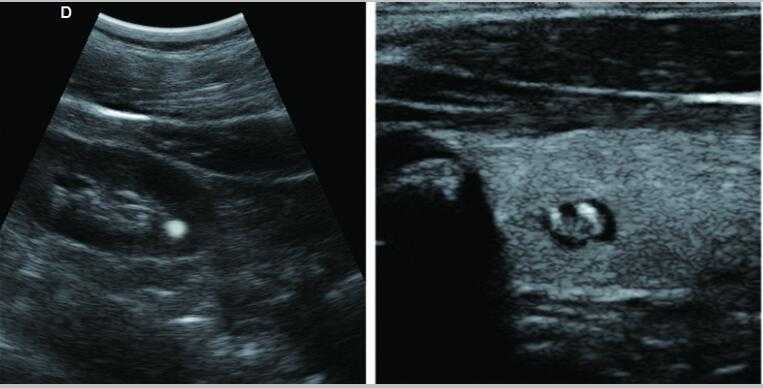

彩色多普勒

采用智能圖像處理技術1.組織諧波成像技術 2.噪聲抑制斑點技術 3.多波束并行處理技術等

7.應用:腹部、婦科、產科、心臟、血管和小器官、泌尿科、肌肉骨骼、兒科等